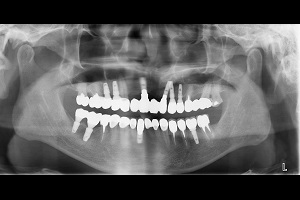

治療前-多顆缺牙及牙周病、蛀牙

人工植牙與全口治療